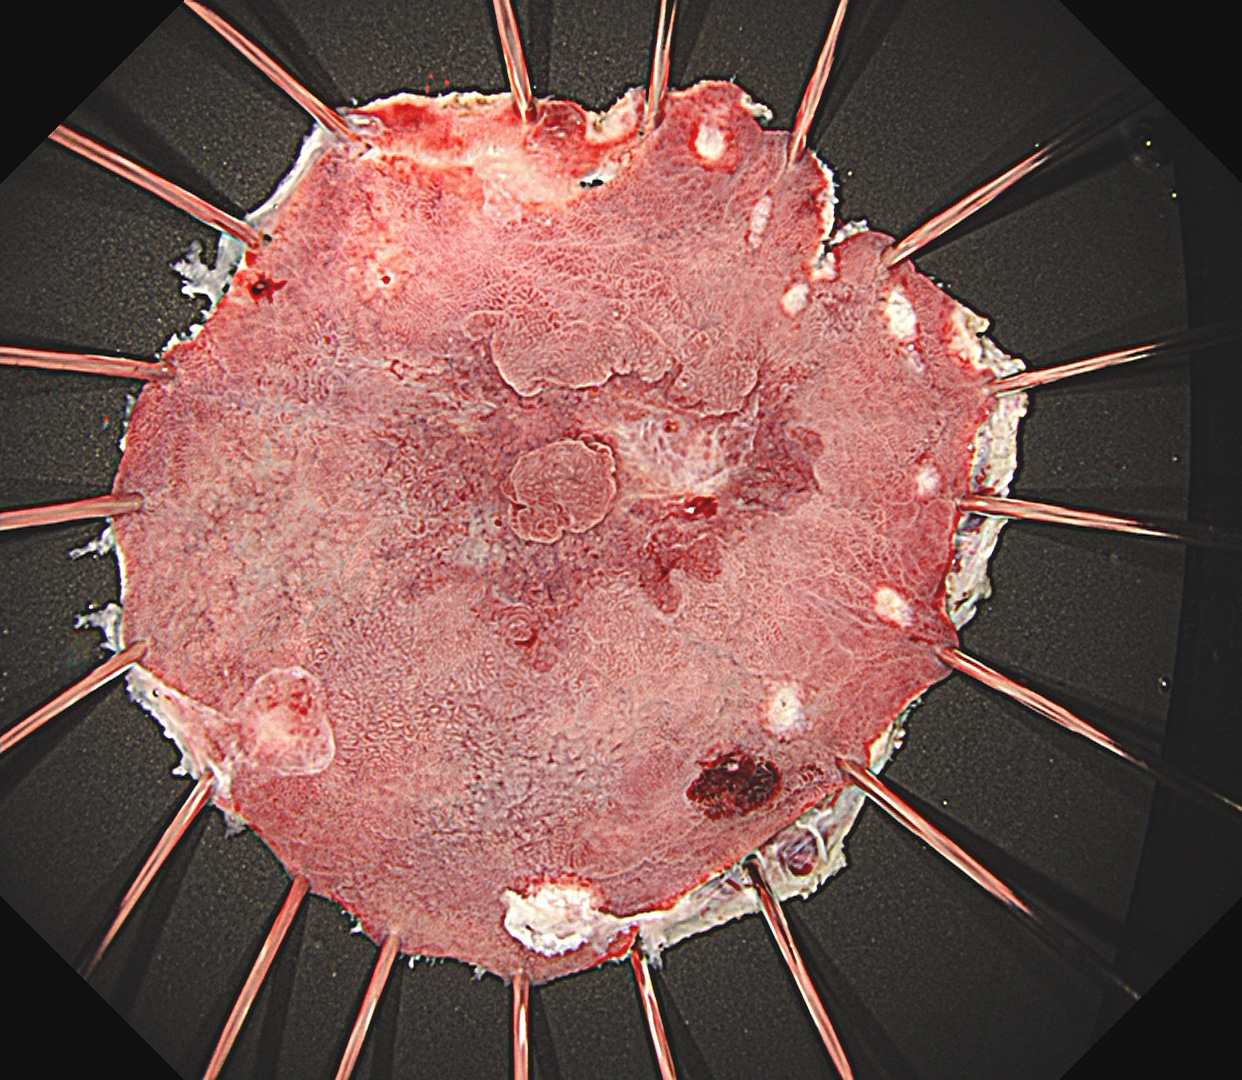

- EMR・ESD による早期消化管癌の低侵襲治療

早期胃癌(SM浸潤がん)ESD